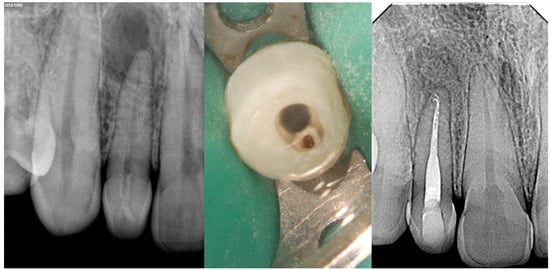

- Type III

| Type IIIa/IIIb | High risk of periapical/periodontal infection | CBCT essential to determine anatomy and extent | Selective treatment of infected invagination if pulp unaffected Often requires surgical access and debridement Orthograde or retrograde obturation with biocompatible materials Combined endodontic and periodontal approach in complex cases | Prognosis depends on anatomical complexity and extent of infection Long-term monitoring essential due to risk of reinfection |